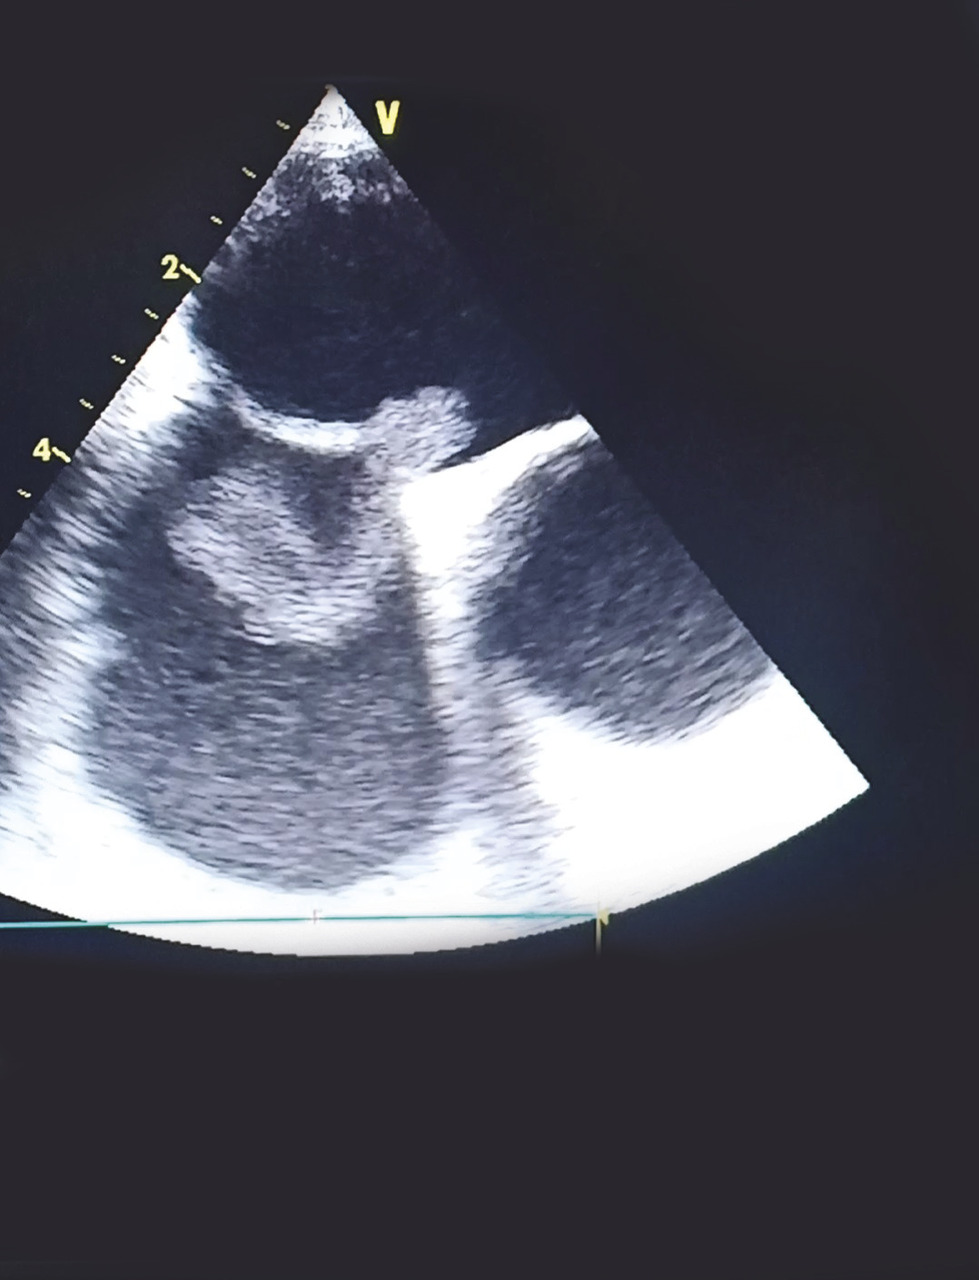

Cet homme de 37 ans était hospitalisé pour une hémiplégie gauche, 40 jours après ostéosynthèse d’une fracture du tibia droit. Son état hémodynamique et respiratoire était stable lors de son admission, avec des signes de thrombophlébite du membre inférieur droit et un rythme régulier sinusal à l’électrocardiogramme. La tomodensitométrie cérébrale montrait une plage ischémique temporo-pariétale droite. L’échocardiographie visualisait un thrombus mobile enclavé dans le foramen ovale perméable. Le patient était mis sous traitement anticoagulant ; une thrombectomie chirurgicale était réalisée avec fermeture du foramen ovale. Les suites opératoires étaient simples.

L’embolie paradoxale à travers un foramen ovale perméable est une cause rare d’accident vasculaire cérébral ischémique. Elle est due à l’embolisation systémique d’un caillot provenant de la circulation veineuse à travers le foramen ovale. Le diagnostic est posé devant la présence d’une thrombose veineuse, une preuve d’embolisation systémique et la démonstration échocardiographique d’une communication anormale entre les circulations droite et gauche.

La visualisation d’un thrombus enclavé dans le foramen ovale est exceptionnelle et augmente la mortalité et le taux de récidive ischémique liée à cette pathologie.1, 2

Le traitement curatif associe une anticoagulation efficace à une thrombectomie chirurgicale avec fermeture du foramen.